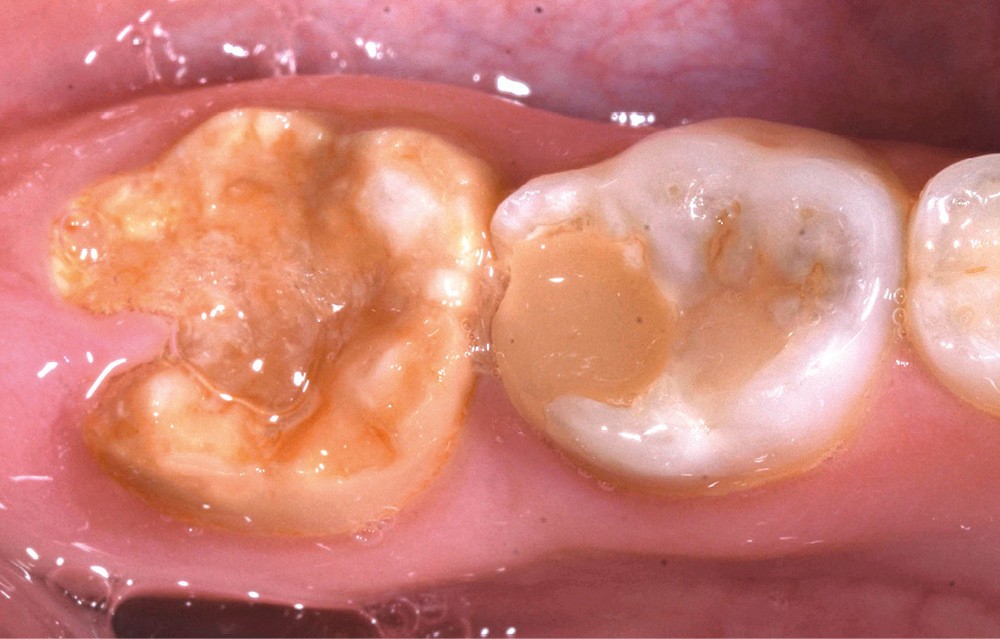

Une patiente de 10 ans se présente en consultation. Aucun antécédent médical ou chirurgical n’est constaté. À l’examen clinique, nous observons une forme sévère de MIH sur 36 et 46 avec des fractures post-éruptives [1] (fig. 1a et b). En raison de cette pathologie, la patiente se plaint de sensibilités spontanées sur ces dents, ayant un impact sur sa qualité de vie, et une maîtrise difficile de l’hygiène bucco-dentaire. Les secteurs antérieurs maxillaires et mandibulaires présentent aussi des opacités délimitées entraînant une gêne esthétique conséquente pour la patiente.